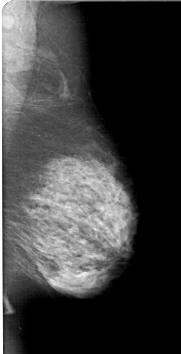

A_1237_1.LEFT_MLO

LESION_TYPE MASS SHAPE IRREGULAR MARGINS SPICULATED

ASSESSMENT 5

SUBTLETY 5

PATHOLOGY MALIGNANT